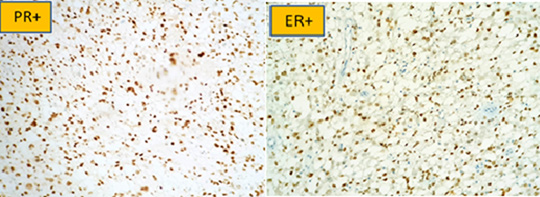

Figure 3: Positivity of progesterone (PR) and estrogenic (ER) hormone receptors in immunohistochemistry.

The CA125 was dosed at 320IU/ml. The laparotomy had revealed an ascites of great abundance, aspirated at 4 liters, a sample for cytological examination was taken, on exploration we found an enormous friable mass at the expense of the left ovary adhering to the wall, omentum and uterus, measuring 30cm long axis, adhesiolysis done with fragmentation of the mass. The liver and stomach are smooth without peritoneal carcinoma nodules.-A left annexectomy was performed removing the mass which was fragmented due to the friability. The right appendix was not seen, hidden by adhesions. Omentectomy as well as multiple biopsies were done. The hysterectomy could not be performed due to the adhesions. Pathological examination of the ovarian mass and omentectomy with immunohistochemical study were carried out. The expression of both epithelial markers (Cytokeratin [CK]/ EMA) and mesenchymal markers (Vimentin / AML / Calretinin) allowed us to make the diagnosis of carcinosarcoma (Figures: 2(a,b),3,4(a,b)).